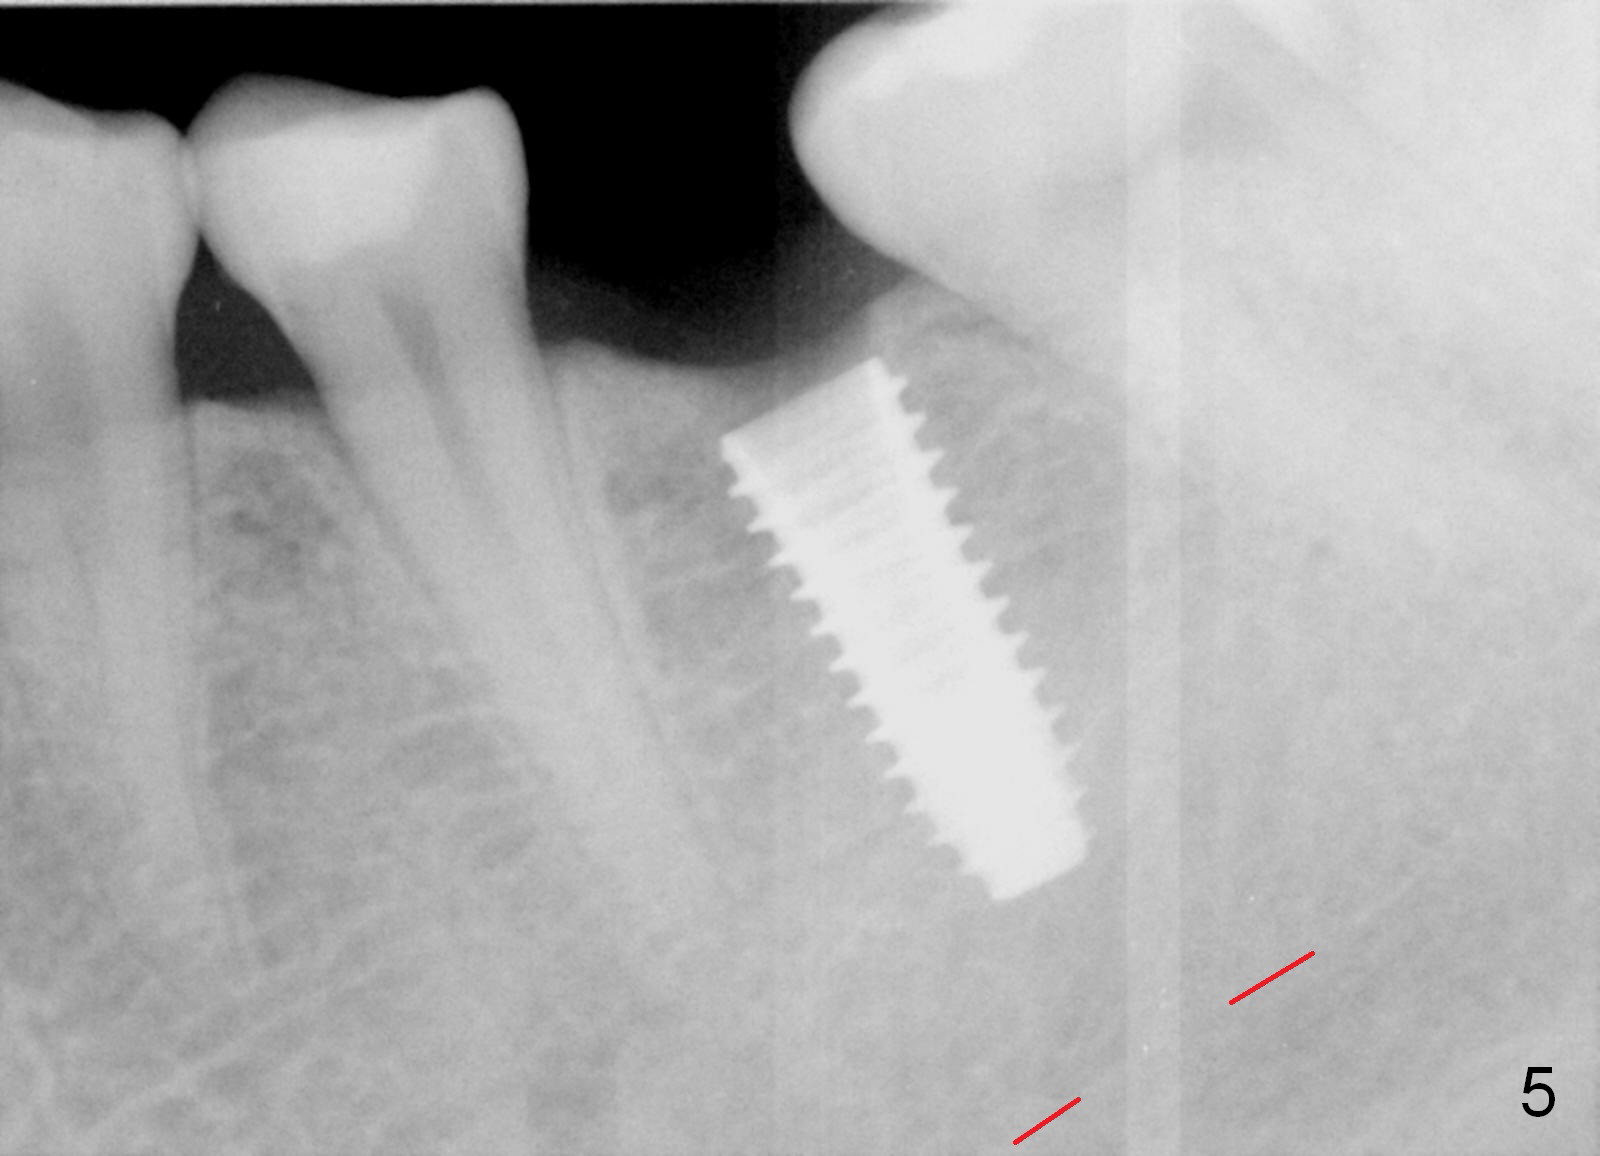

In fact, the buccolingual width of the ridge is sufficient to have a 4.5x11.5 mm implant placed (Fig.4,5, D3 bone, <35 Ncm). Proximal reduction is done before and after placement of a 5.5x4(3) mm abutment. Heavy abutment height adjustment is provided as well as the opposing prior to immediate provisional.

There is no bone loss 3 months postop (Fig.6).